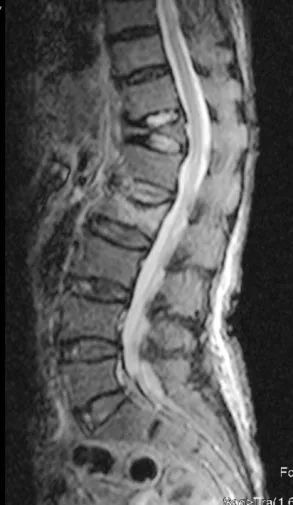

經(jīng)過各種檢查,王阿婆被明確診斷為腰部第二椎體骨折。徐榮敏醫(yī)師、李順東醫(yī)師認(rèn)為王阿婆的身體機(jī)能尚可,如果臥床3月則有眾多并發(fā)癥,身體狀況會進(jìn)一步下降,而行微創(chuàng)手術(shù),則可早期下床活動(dòng),有效減少各類并發(fā)癥。權(quán)衡利弊,覺得阿婆行微創(chuàng)手術(shù)所獲得的收益更大,經(jīng)過與家屬充分溝通,決定行經(jīng)皮穿刺骨水泥成形術(shù)。

手術(shù)要求俯臥位,這對103歲的王阿婆是個(gè)挑戰(zhàn),阿婆脊柱嚴(yán)重側(cè)彎,平時(shí)都是側(cè)著睡,這就要求手術(shù)醫(yī)生盡量縮短手術(shù)時(shí)間。經(jīng)過充分準(zhǔn)備,手術(shù)從穿刺到骨水泥成形成功,歷時(shí)15分鐘。